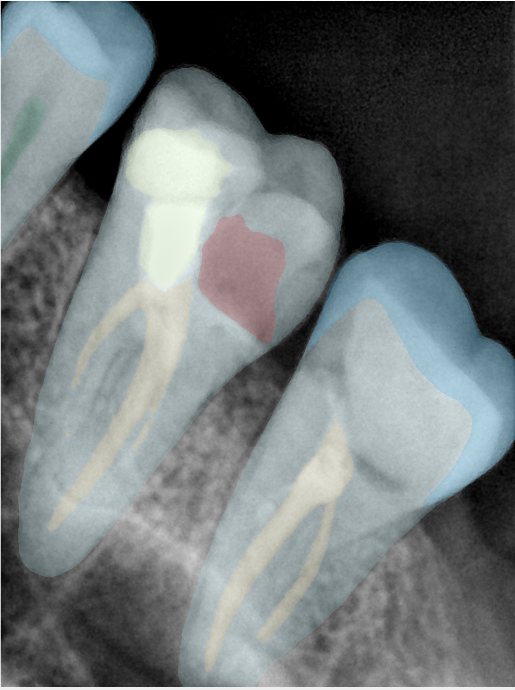

第二版算法问题测试

| 第一版 | 第二版 | 是否解决 | |

|---|---|---|---|

![]() | ![]() ![]() 边角识别有问题 龋齿识别不全 牙髓识别不全 | ![]() | 解决 |

![]() | ![]() 边角识别有问题 识别信息有误 自查(牙冠识别不全) | ![]() | 解决 |

![]() | ![]() ![]() 边角识别有误 大范围填充识别遗漏 | ![]() | 解决 |

![]() | ![]() 识别信息不全 | ![]() | 解决 |

![]() | ![]() ![]() 边角问题 牙胶识别不全 牙冠识别不全 | ![]() | 解决 |

![]() 换图片 | ![]() | ![]() 牙冠部分稍微白了一些就识别成小范围修补,部分判断异常 | 部分解决,修复类略敏感,牙冠部分稍微白了一些就识别成小范围修补,部分判断异常。 |

![]() | ![]() ![]() 牙冠识别不全 牙髓不全 根尖炎龋齿识别有误 | ![]() | 解决 |

![]() | ![]() | ![]() | 解决 |

![]() 换图片 | ![]() | ![]() | 解决 |

![]() | ![]() 牙冠识别有误 | ![]() | 解决 |

![]() 换图片 | ![]() ![]() 边角识别有误 | ![]() 修复类敏感 | 部分解决,图像过白,导致修复类判断异常。 |

![]() 换图片 | ![]() 牙冠识别不全 | ![]() 修复类敏感 | 部分解决,图像过白,导致修复类判断异常 |

结论:修复类出现了不鲁棒的情况,后续需要加入轮廓的扩充数据进行增强。